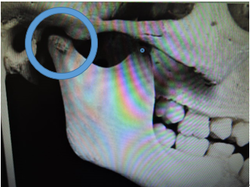

全ての歯が萌え揃うと顎の関節は写真の様に骨で固まってしまいます。

この為、下顎骨が後ろに後退し生じた出っ歯などは非抜歯での治療が難しくなります。

このため下顎骨が後ろに後退したために生じた出っ歯などは、非抜歯での治療が難しくなります。